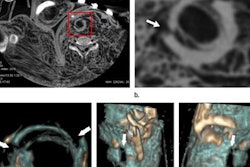

The book Vogel wrote with B.G. Brogdon and John McDowell.Along with B.G. Brogdon and John McDowell, Vogel wrote the classic textbook about the radiology of abuse, torture, terrorism, and inflicted trauma, which included over 700 large radiographs related to clinical forensic medicine and the detection of concealed arms, explosives, and other weapons. It gave details about the latest modalities for evaluation and identification of victims, and included more than 30 color photos and specimens with virtual autopsy radiographs from MRI and CT.